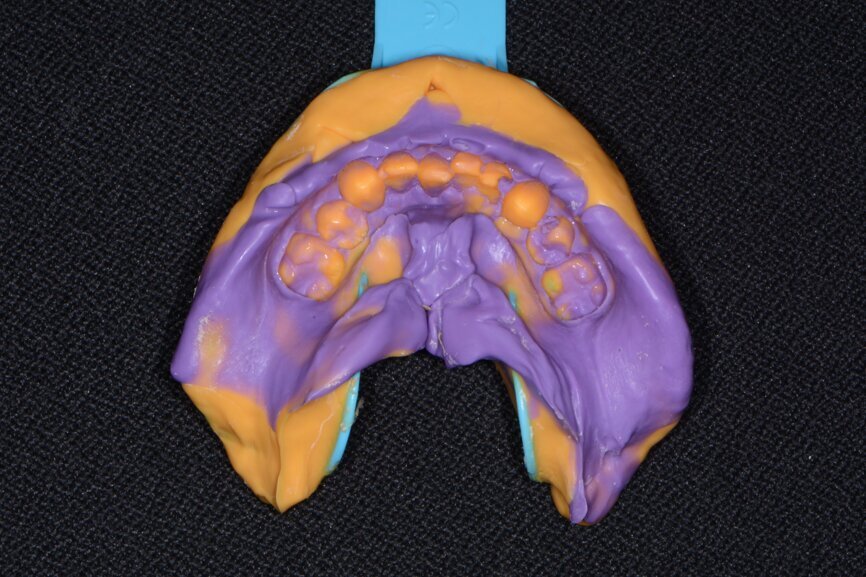

Fig. 7: Maxillary impression (Kettenbach).

To further develop a treatment plan, diagnostic model impressions were taken using Panasil (Kettenbach) Heavy Body and Light Body polyvinylsiloxane impression material (Figs. 7 & 8), poured up and forwarded to the dental laboratory. These models were then mounted on an articulator (Stratos 100, Ivoclar Vivadent) for further analysis in order to meet the patient’s aesthetic and functional needs.